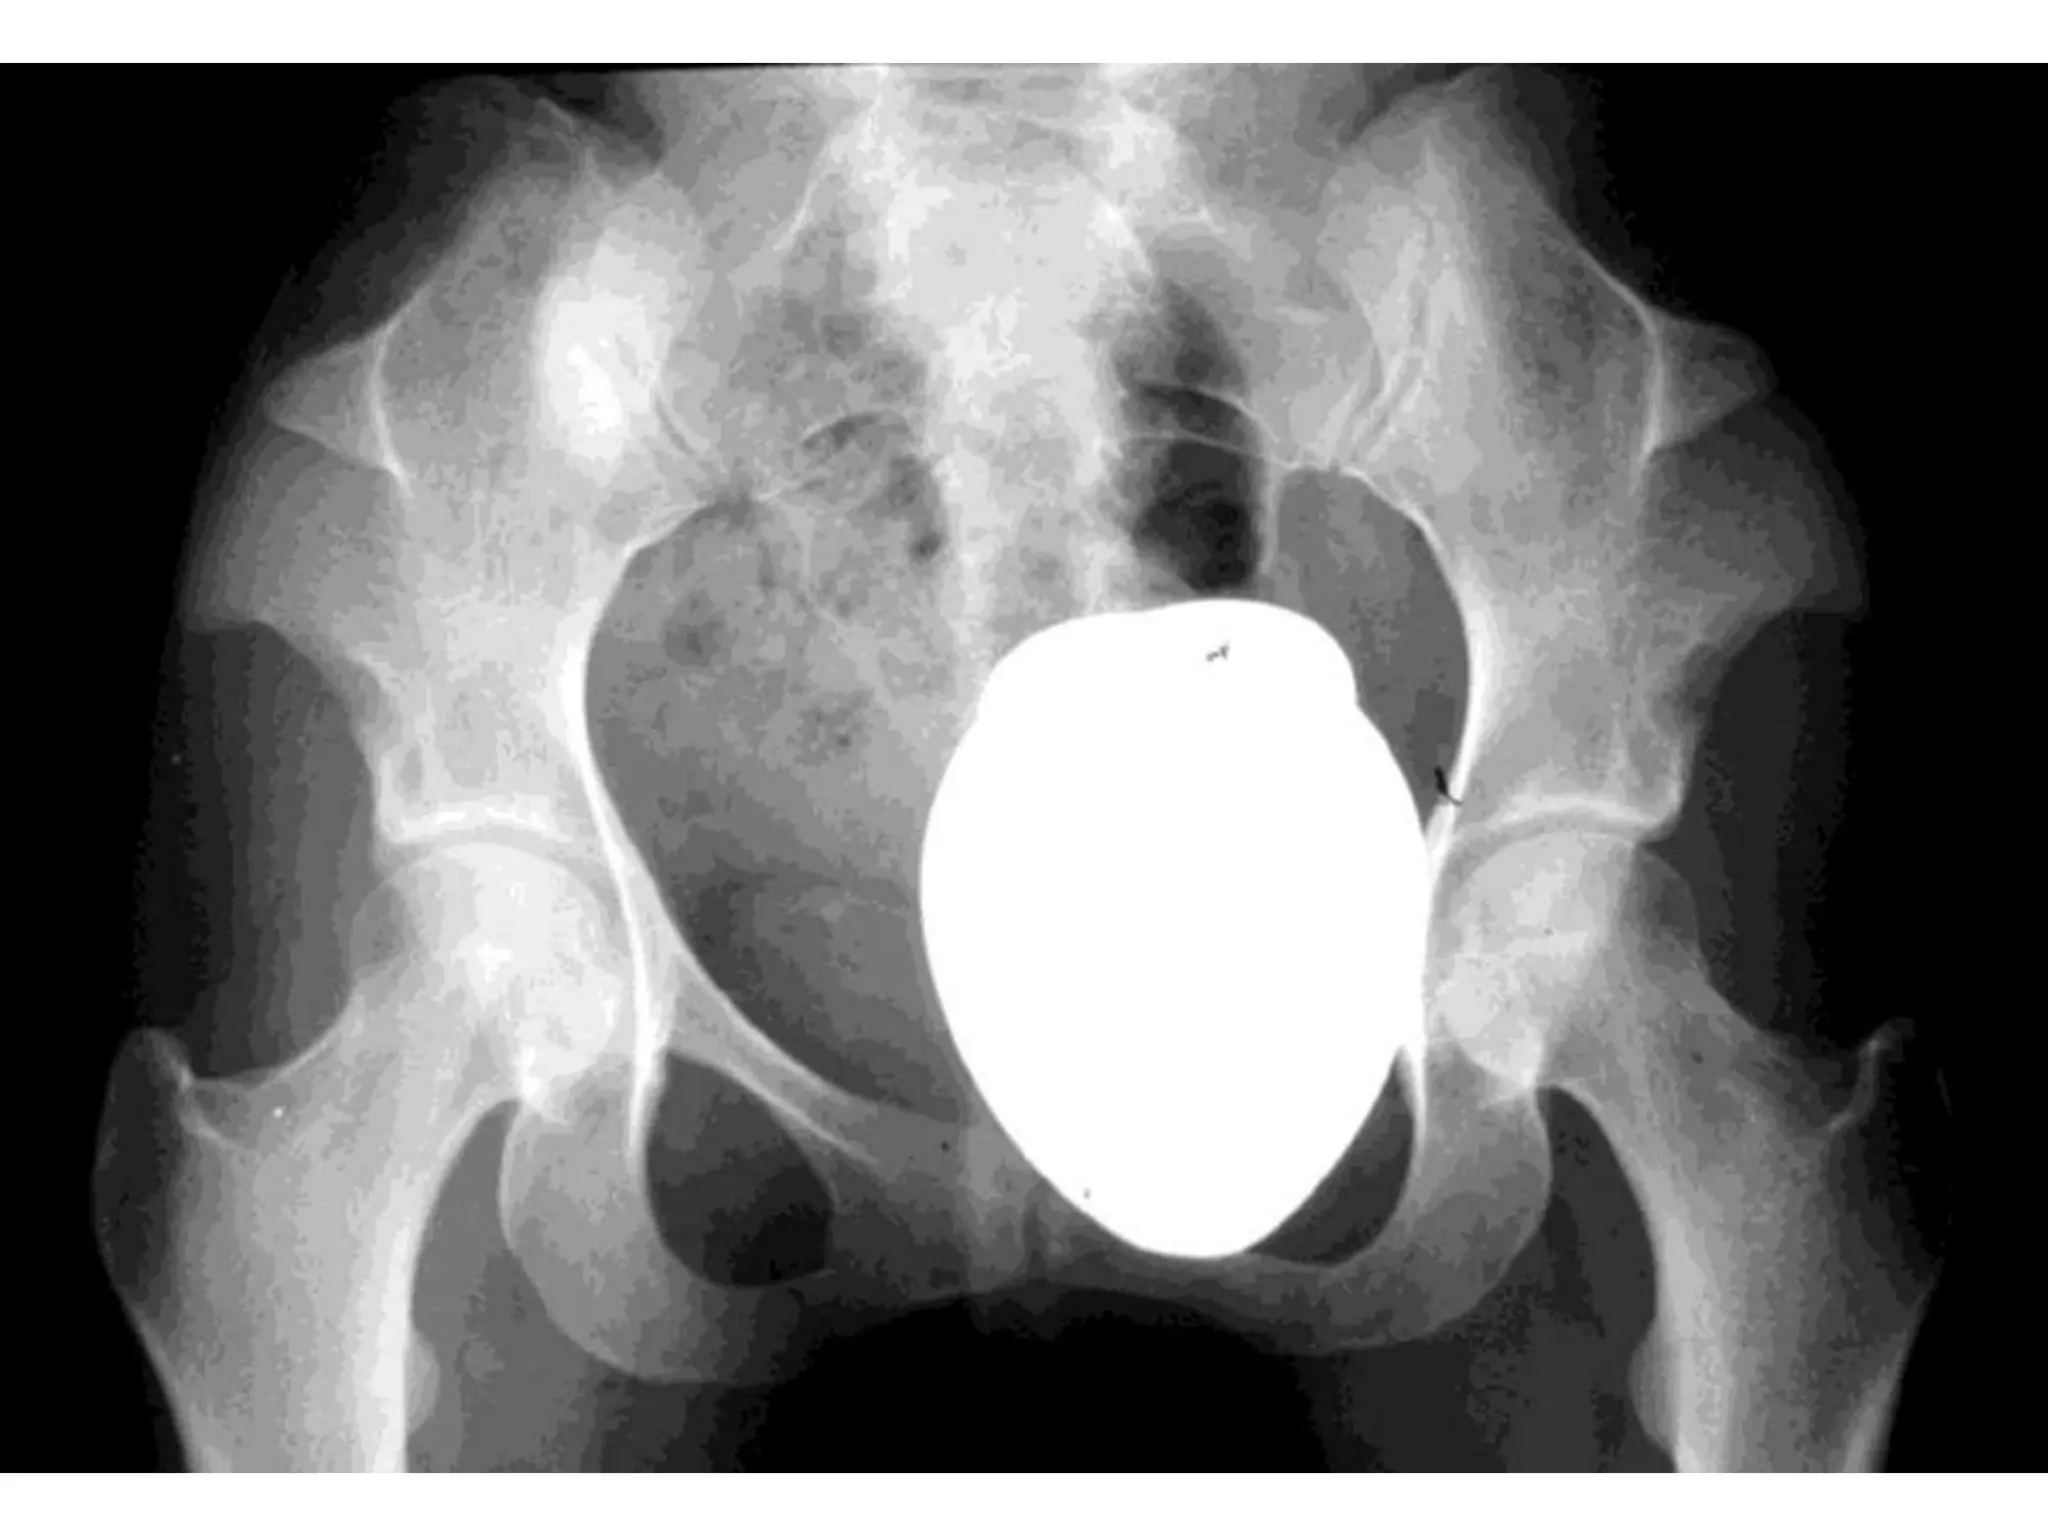

• Xray : pelvis flattening

Hypochondroplasia • Mild formof achondroplasia • Stocky individuals • Xray : pelvis flattening thickening of long bones Treatment: Limb lengthening